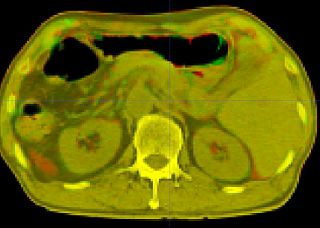

Registration of abdomen.

Registration output in Slicer